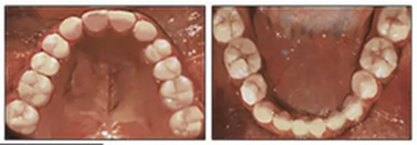

治療持續(xù)3年,患者始終保持積極和合作。口腔衛(wèi)生很好?;颊吆退母改付紝Y(jié)果感到滿意。經(jīng)過24個月的保持后,咬合保持得很好(圖11 ; 圖12)。在上牙弓中,應(yīng)用固定舌側(cè)保持器以防止任何復(fù)發(fā)傾向。在下牙弓中,治療后拔除第三磨牙。